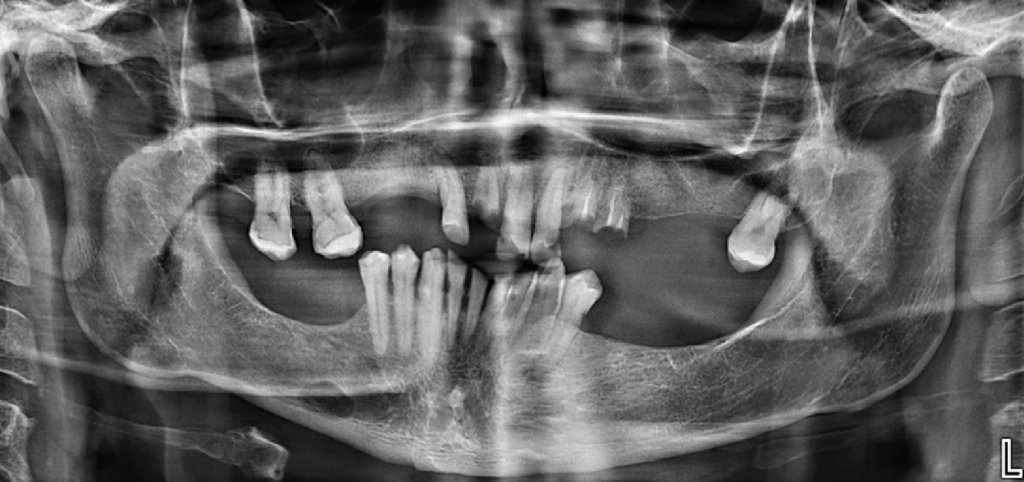

Radiografia Panorámica

A la evaluación de la radiografía panorámica se observa la neumatización de ambos senos maxilares, paciente presenta Edentulismo parcial, presencia de placa cervical mineralizada y reabsorción ósea moderada del proceso alveolar, así como múltiples restauraciones coronarias y piezas dentarias del sector anterior superior e inferior con pérdida de estructura coronaria.

Asimismo, se observa una imagen radiolúcida de forma ovalada y corticalizada proyectada en cuerpo mandibular del lado derecho próxima al reborde basal.